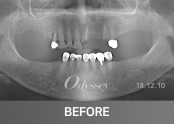

임플란트 181210

임플란트 181229

임플란트 181105

임플란트 181208